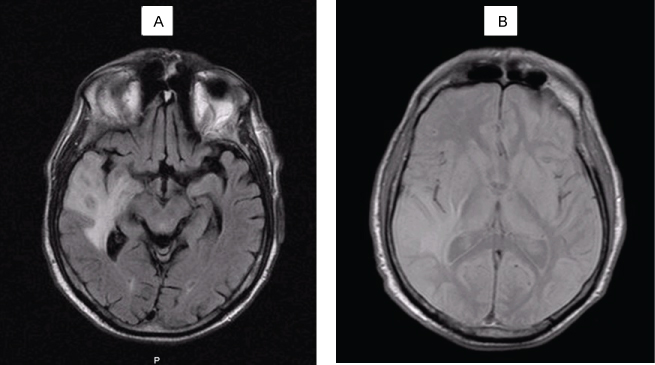

Five months after the diagnosis, he was rushed to emergency hospital with tonic-clonic seizures and a head CT revealed a "right subcortical temporal hyperdense expansive lesion, with central necrosis and peri lesional edema" (Figure 4). This was further confirmed by magnetic resonance (MRI), which also excluded secondary lesions (Figure 5).

Figure 4: Head CT: right subcortical temporal hyperdense expansive lesion, with central necrosis and peri lesional edema. View Figure 4

Figure 5: Head MRI: intra-axial lesion, round, 13 mm diameter, cortical-subcortical transition of anterior region of the right superior temporal circumvallation. The aspect is solid, hipointense on T1 (A) and isointense with grey substance on T2 (B), with moderate reinforce with gadolinium injection. Extensive perilesional vasogenic edema on the right temporal lobe. View Figure 5

The tumor was restaged as stage IV. He was submitted to metastasis ablation with gamma knife radiosurgery, however there was progression of the lesion on subsequent head CT’s. Once again, he presented with polyarthritis of hands and wrists and proximal muscle weakness of the scapular belt, which maintained.